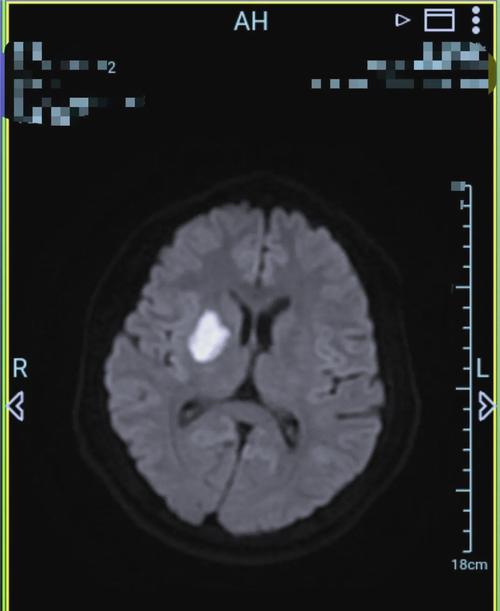

(图片来源网络,侵删)- 弥散加权成像 (DWI) 和 表观弥散系数 (ADC):

- 急性期脑梗塞:在DWI上呈明显高信号,而在ADC图上呈低信号,这是诊断急性脑梗塞的“金标准”。

- 弥散加权成像 (DWI) 和 表观弥散系数 (ADC):

| 超急性期 (< 6小时) | 极高信号 | 低信号 | 可能正常 | 正常 | 正常 |

| 急性期 (6-24小时) | 高信号 | 低信号 | 可能正常或稍高 | 正常 | 稍高信号 |